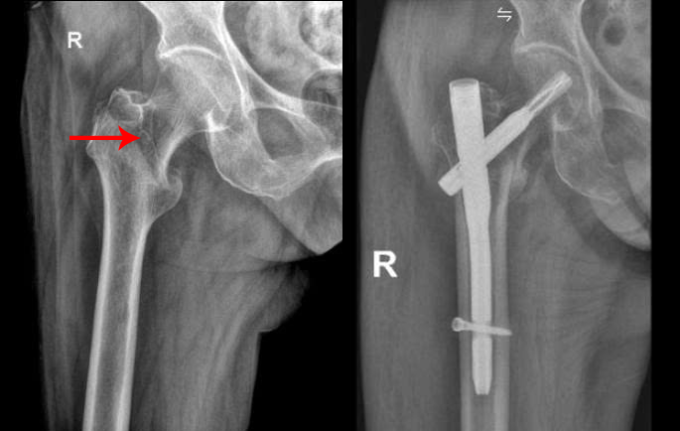

Ổ gãy liên mấu chuyển xương đùi của cụ Lộc trước và sau phẫu thuật. Ảnh: Bệnh viện Đa khoa Tâm Anh

Khám sàng lọc đa chuyên khoa trước mổ cho cụ Lộc, bác sĩ phát hiện một nhánh mạch vành hẹp đến 80-90% và tính toán liều gây mê phù hợp. Êkíp sử dụng bàn mổ chỉnh hình, nắn chỉnh, kiểm tra ổ gãy liên mấu chuyển xương đùi dưới màn hình tăng sáng và hệ thống X-quang di động (C-arm), đưa người bệnh về tư thế mổ thuận lợi nhất nhằm rút ngắn thời gian phẫu thuật.

Trong 40 phút, bác sĩ rạch các đường mổ nhỏ 2-3 cm phía ngoài ổ gãy, đóng đinh nội tủy, bắt vít cố định liên mấu chuyển xương đùi, đóng vết mổ. Phương pháp xâm lấn tối thiểu, giảm nguy cơ trong và sau mổ như mất máu, biến chứng tim mạch cho người bệnh.